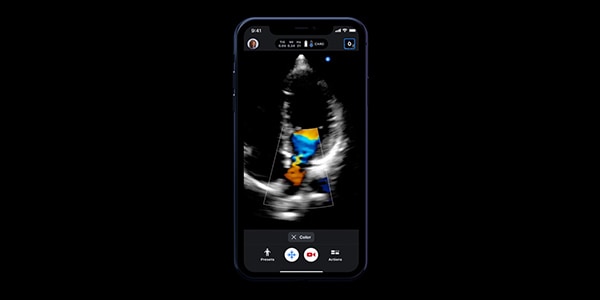

Experience a groundbreaking ultrasound solution and the world's only single-probe, whole-body handheld device, powered by Ultrasound-on-Chip™ technology. Butterfly transforms complex processes into one connected ultrasound system to help you offer better, more efficient care.

Discover Butterfly iQ+ and how it can make ultrasound easier to use. Plug the probe in your compatible device, select from the available presets in seconds with the swipe of a finger — and start scanning.

• Color Doppler: Color Doppler uses standard ultrasound methods to convert Doppler sounds into colors that are overlaid on the image of the blood vessel. These colors represent the qualitative parameters of haemodynamic behavior and direction of blood flow through the vessel.